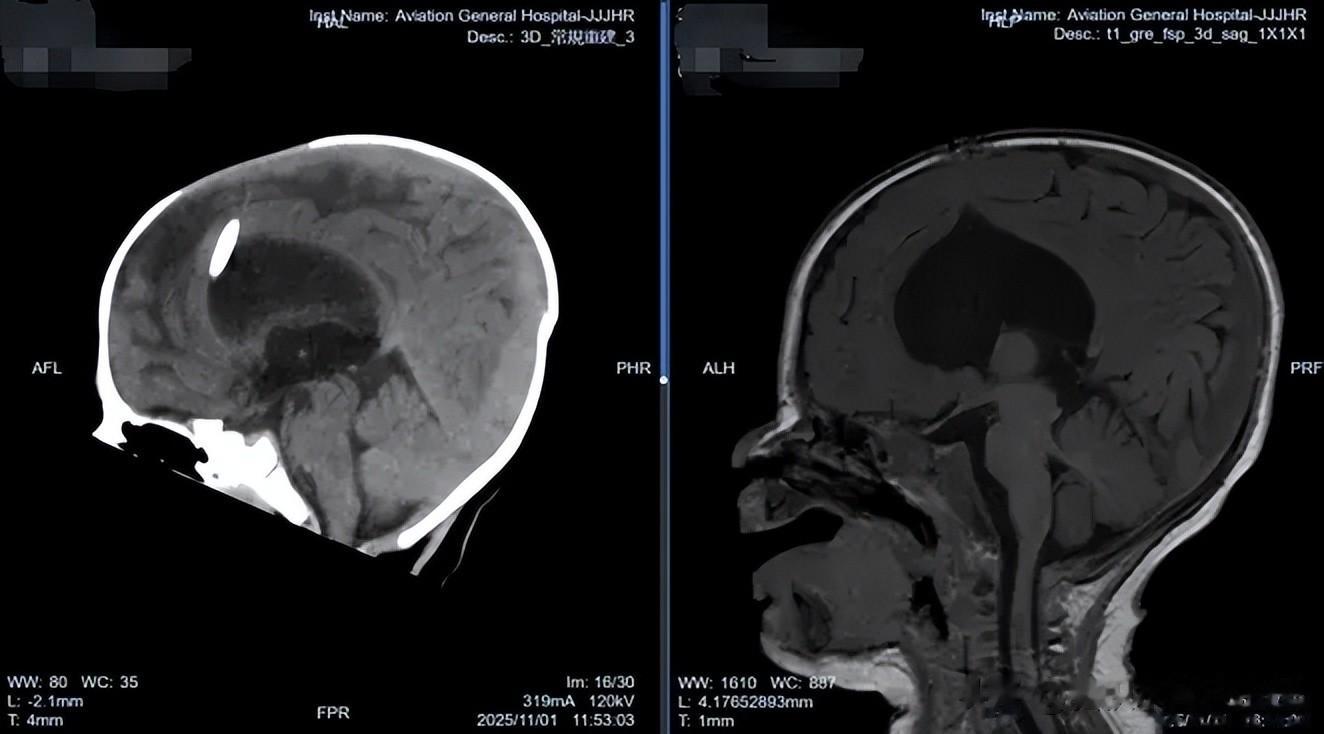

面对患儿的复杂情况,肖庆主任没有急于制定手术方案,而是凭借丰富的临床经验,首先深入了解孩子的全面健康状况,初诊断考虑颅内脑脊液异常,明确的颅内感染证据是治疗的关键。

随后于 2025 年 11 月 6 日在全麻下为患儿实施了神经内镜下第三脑室底造瘘术 + 原分流管去除术。术中留取原分流管管头培养,回报表皮葡萄球菌(+),这一发现证实了术前的感染判断,也解释了为何初次分流术后患儿症状未见改善。